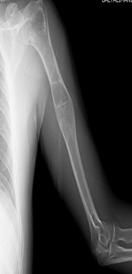

Kemikte aşırı zayıflık oluşunca patolojik kırık gelişebilir. Uyluk kemiği üst ucunda lezyonun geliştiği fark edilmez ise çoban asası görüntüsü meydana gelir. Düz grafide buzlu cam görüntüsü tipiktir. Genellikle hastaların şikayeti yoktur. Şişlik ve ağrı şikayeti gelişebilir. Fibröz displazi iskelet sisteminin gelişimi ile birlikte büyür. İskelet büyümesi tamamlanınca lezyonun gelişimi yavaşlar.

Fibröz displazinin altı aylık aralarla alınacak filmlerlekontrolu yapılır. Bifosfanatlar medikal tedavide altın standarttır. Patolojik kırık veya patolojik kırık gelişme ihtimali yüksek olduğunda kanal içi çivileme ile tedavi edilir. Deformite geliştiğinde düzeltici osteotomi ve internal osteosentez uygulanır. Cerrahi tedavide; küretaj +grefonaj, yüksek nüks nedeni ile gözardı edilir, kanal içi osteosentez uygulanır. Ayrıca deformitenin gelişmesini engellemek için de geniş lezyonlarda koruyucu internal fiksasyon da yapılır. Büyüme kıkırdaklarının aktif olduğu dönemlerde intramedüller çivileme bu bölgelere zarar verebilir. Tedavide amaç deformitelerin oluşmasını engellemek ve var olanı düzeltmektir. Monostotik formlarda %0,4 oranında kötü huylu tümöre (malignite) dönüş bildirilmiştir.